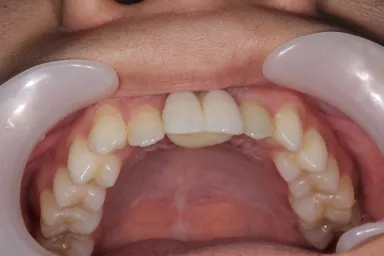

親知らずの移植後

<症例(19歳男性)>

自転車転倒により上の前歯を喪失した患者で入れ歯を入れるも紛失し、インプラント治療以外で治療法がないかと移植に希望をもって当院へ来院されました。当初は下の両側の小臼歯2本を移植し、矯正で抜いた部分を閉鎖しようと検討したものの、矯正医よりスペースの閉鎖は困難と診断され断念。家族、本人の熱意もあり、「埋伏の親知らず」を移植する計画を立て、3D-CTと3Dプリンターを用いての精密なシミュレーションを行った上で施術を行いました。

3D-CT、3Dプリンターがない時代は、手術後が全く予想できず、考えたとしても空論でしかなく、また今まで論文も存在しないため、本症例は世界で初めての施術例となります。本症例につきまして、3月21日(木)に開催される以下学会において発表させて頂きます。